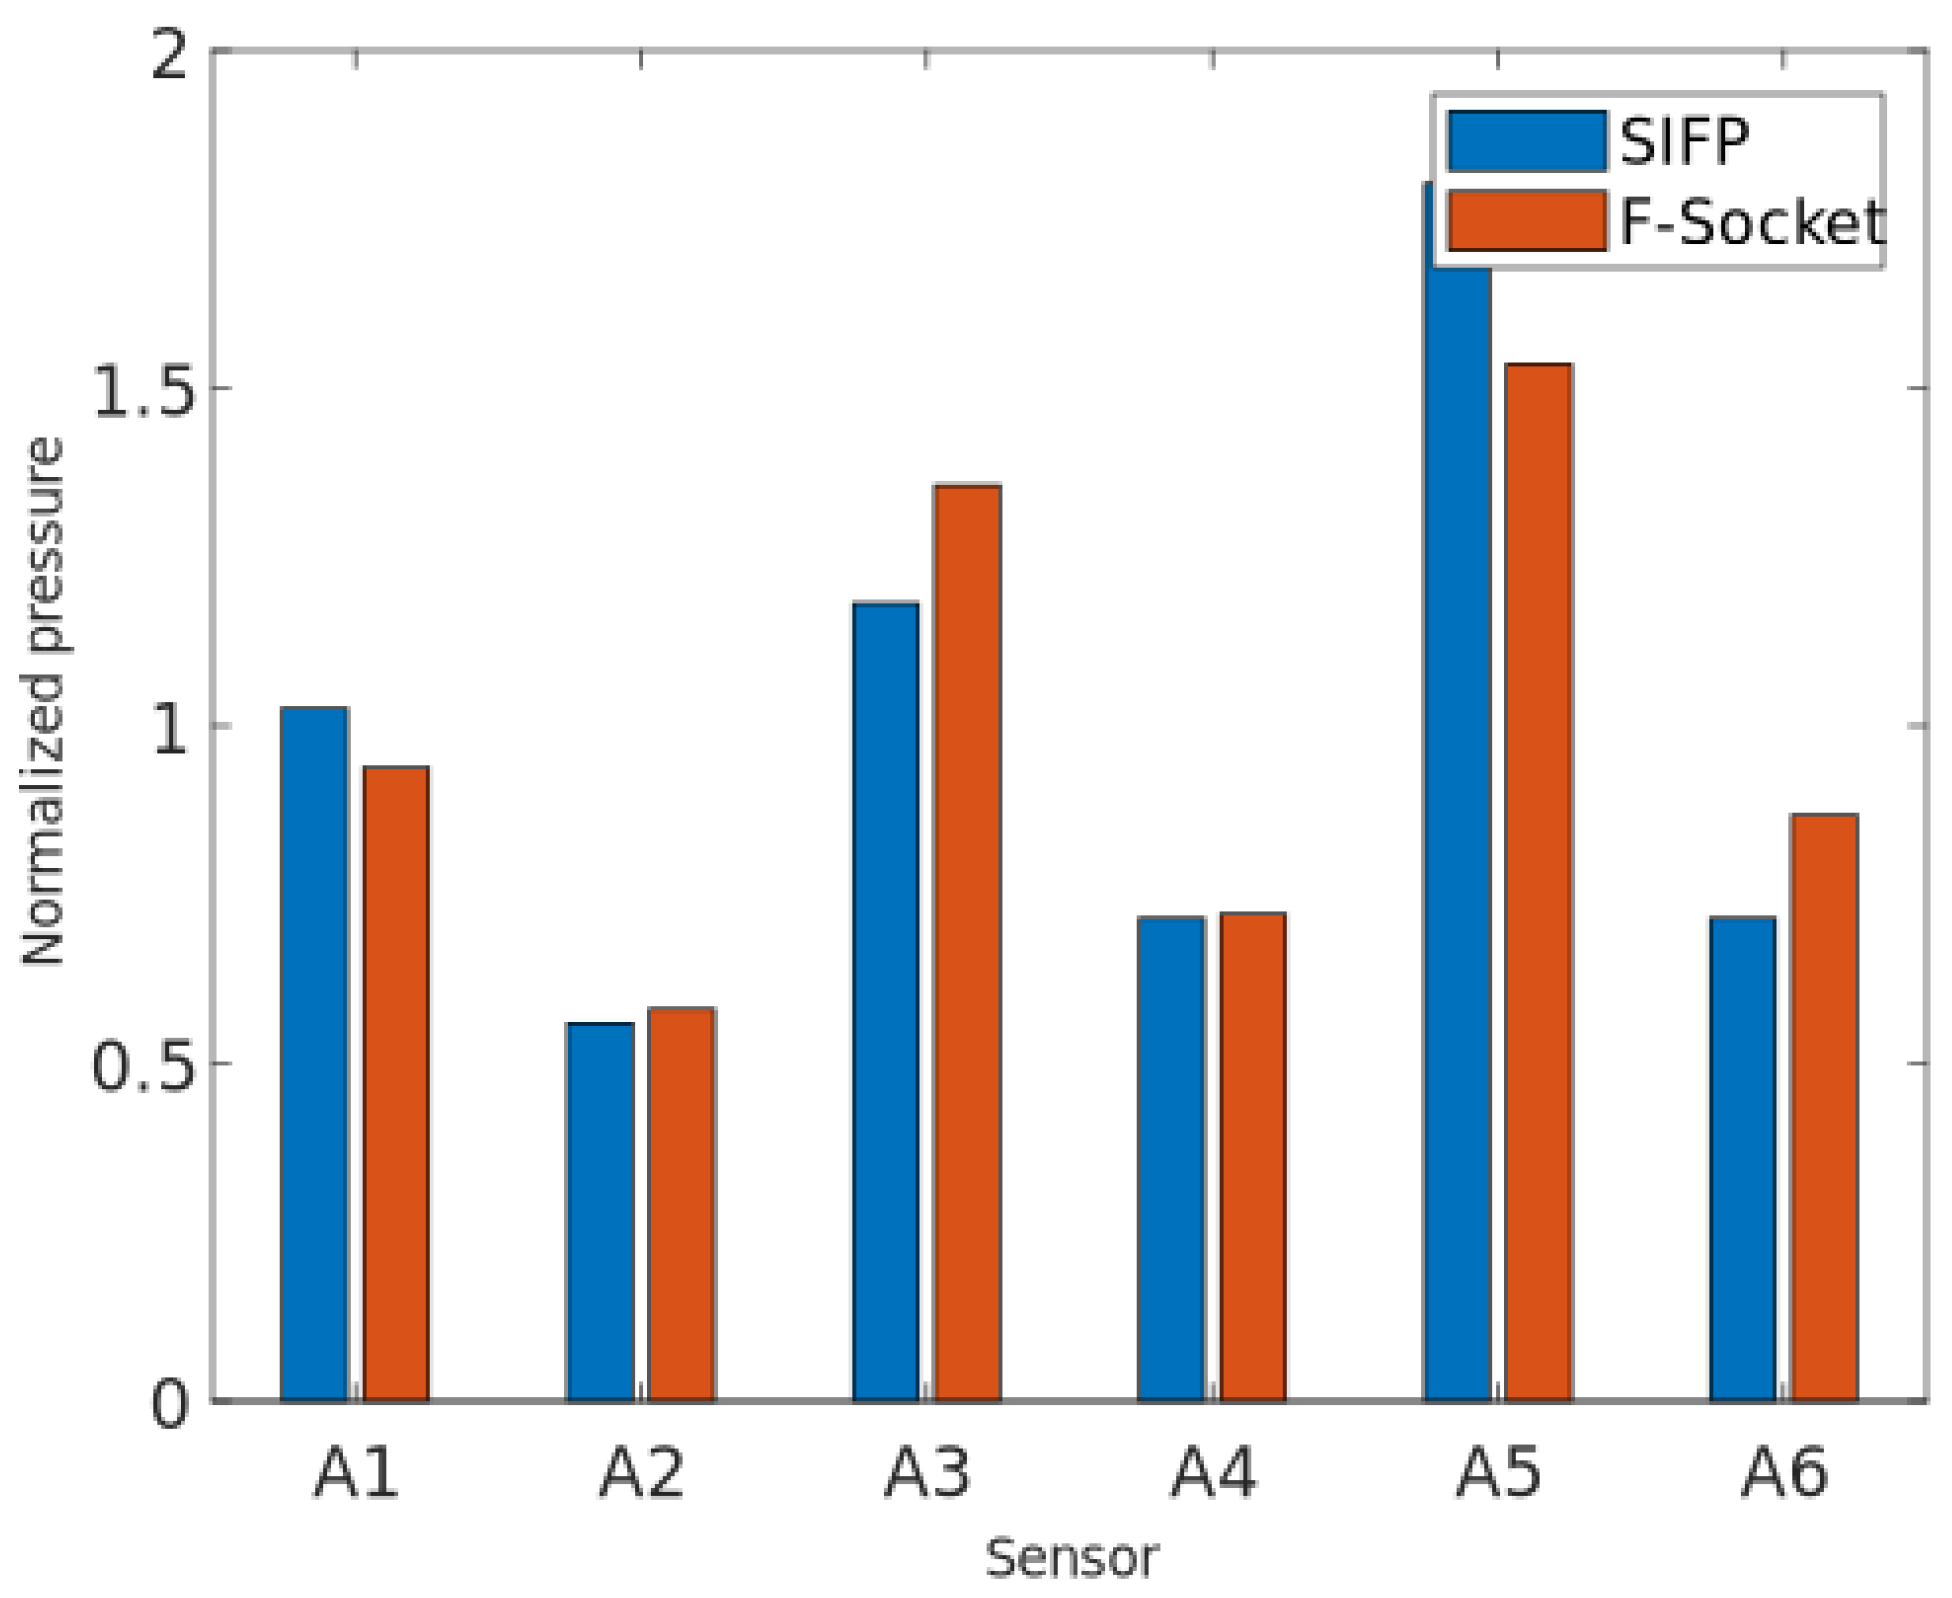

3.2. Comparison Results between F-Socket System and Socket Interface Pressure Device